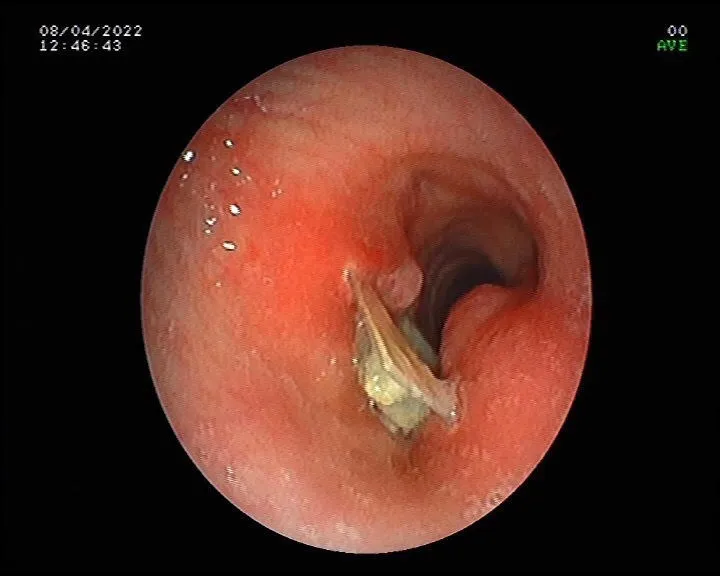

Ho kéo dài do dị vật đường thở ảnh 4 Hình ảnh dị vật sau khi lấy ra khỏi đường thở qua nội soi

Ngày 4-4, bệnh nhân đến Trung tâm Y khoa Thiện Nhân Đà Nẵng để khám. Qua khám lâm sàng, bệnh nhân không có tiền sử hen phế quản, không hút thuốc và chưa từng điều trị bệnh phổi trước đây. Khai thác bệnh lý phát hiện ho kéo dài xuất hiện sau một lần uống thuốc quên bóc vỏ, lúc đầu ho ra đàm lẫn bột trắng, nghĩ đã khạc vỏ thuốc ra ngoài. Ho kéo dài, thở có lúc khò khè, lúc khạc đàm có ít máu... Nghi dị vật đường thở, bệnh nhân được chỉ định chụp CT ngực, kết quả phát hiện dị vật nằm ở khí quản gây hẹp không hoàn toàn đường thở. Bệnh nhân đã được nội soi phế quản, gắp dị vật ra khỏi khí quản.